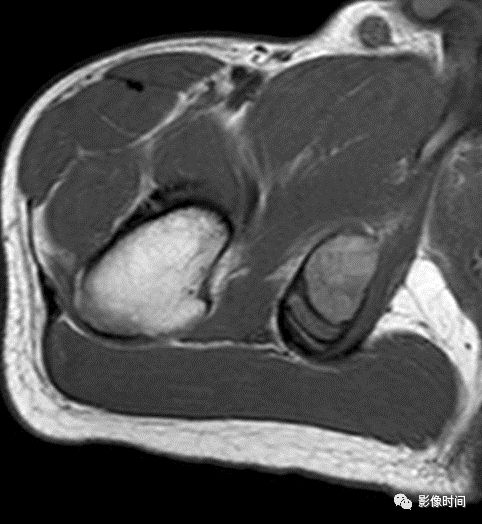

(二)瘤软骨  为肿瘤细胞产生的软骨基质,多来源于软骨类肿瘤,或内有化生瘤软骨成分的其他肿瘤如成软骨型骨肉瘤。瘤软骨为软组织密度,未钙化时,主要通过 MRI 检查显示。

由于瘤软骨多由富含水分及粘多糖的透明软骨构成,故 T1WI 呈偏低信号,T2WI 或 PDWI 呈明显高信号,被低信号的纤维间隔分开呈分叶状(图 24、图 25a-b),增强扫描多呈不均匀分隔状强化(图 25c),主要是纤维间隔强化,瘤软骨强化不明显之故。

图 24  瘤软骨:内生软骨瘤

图 25  瘤软骨:内生软骨瘤